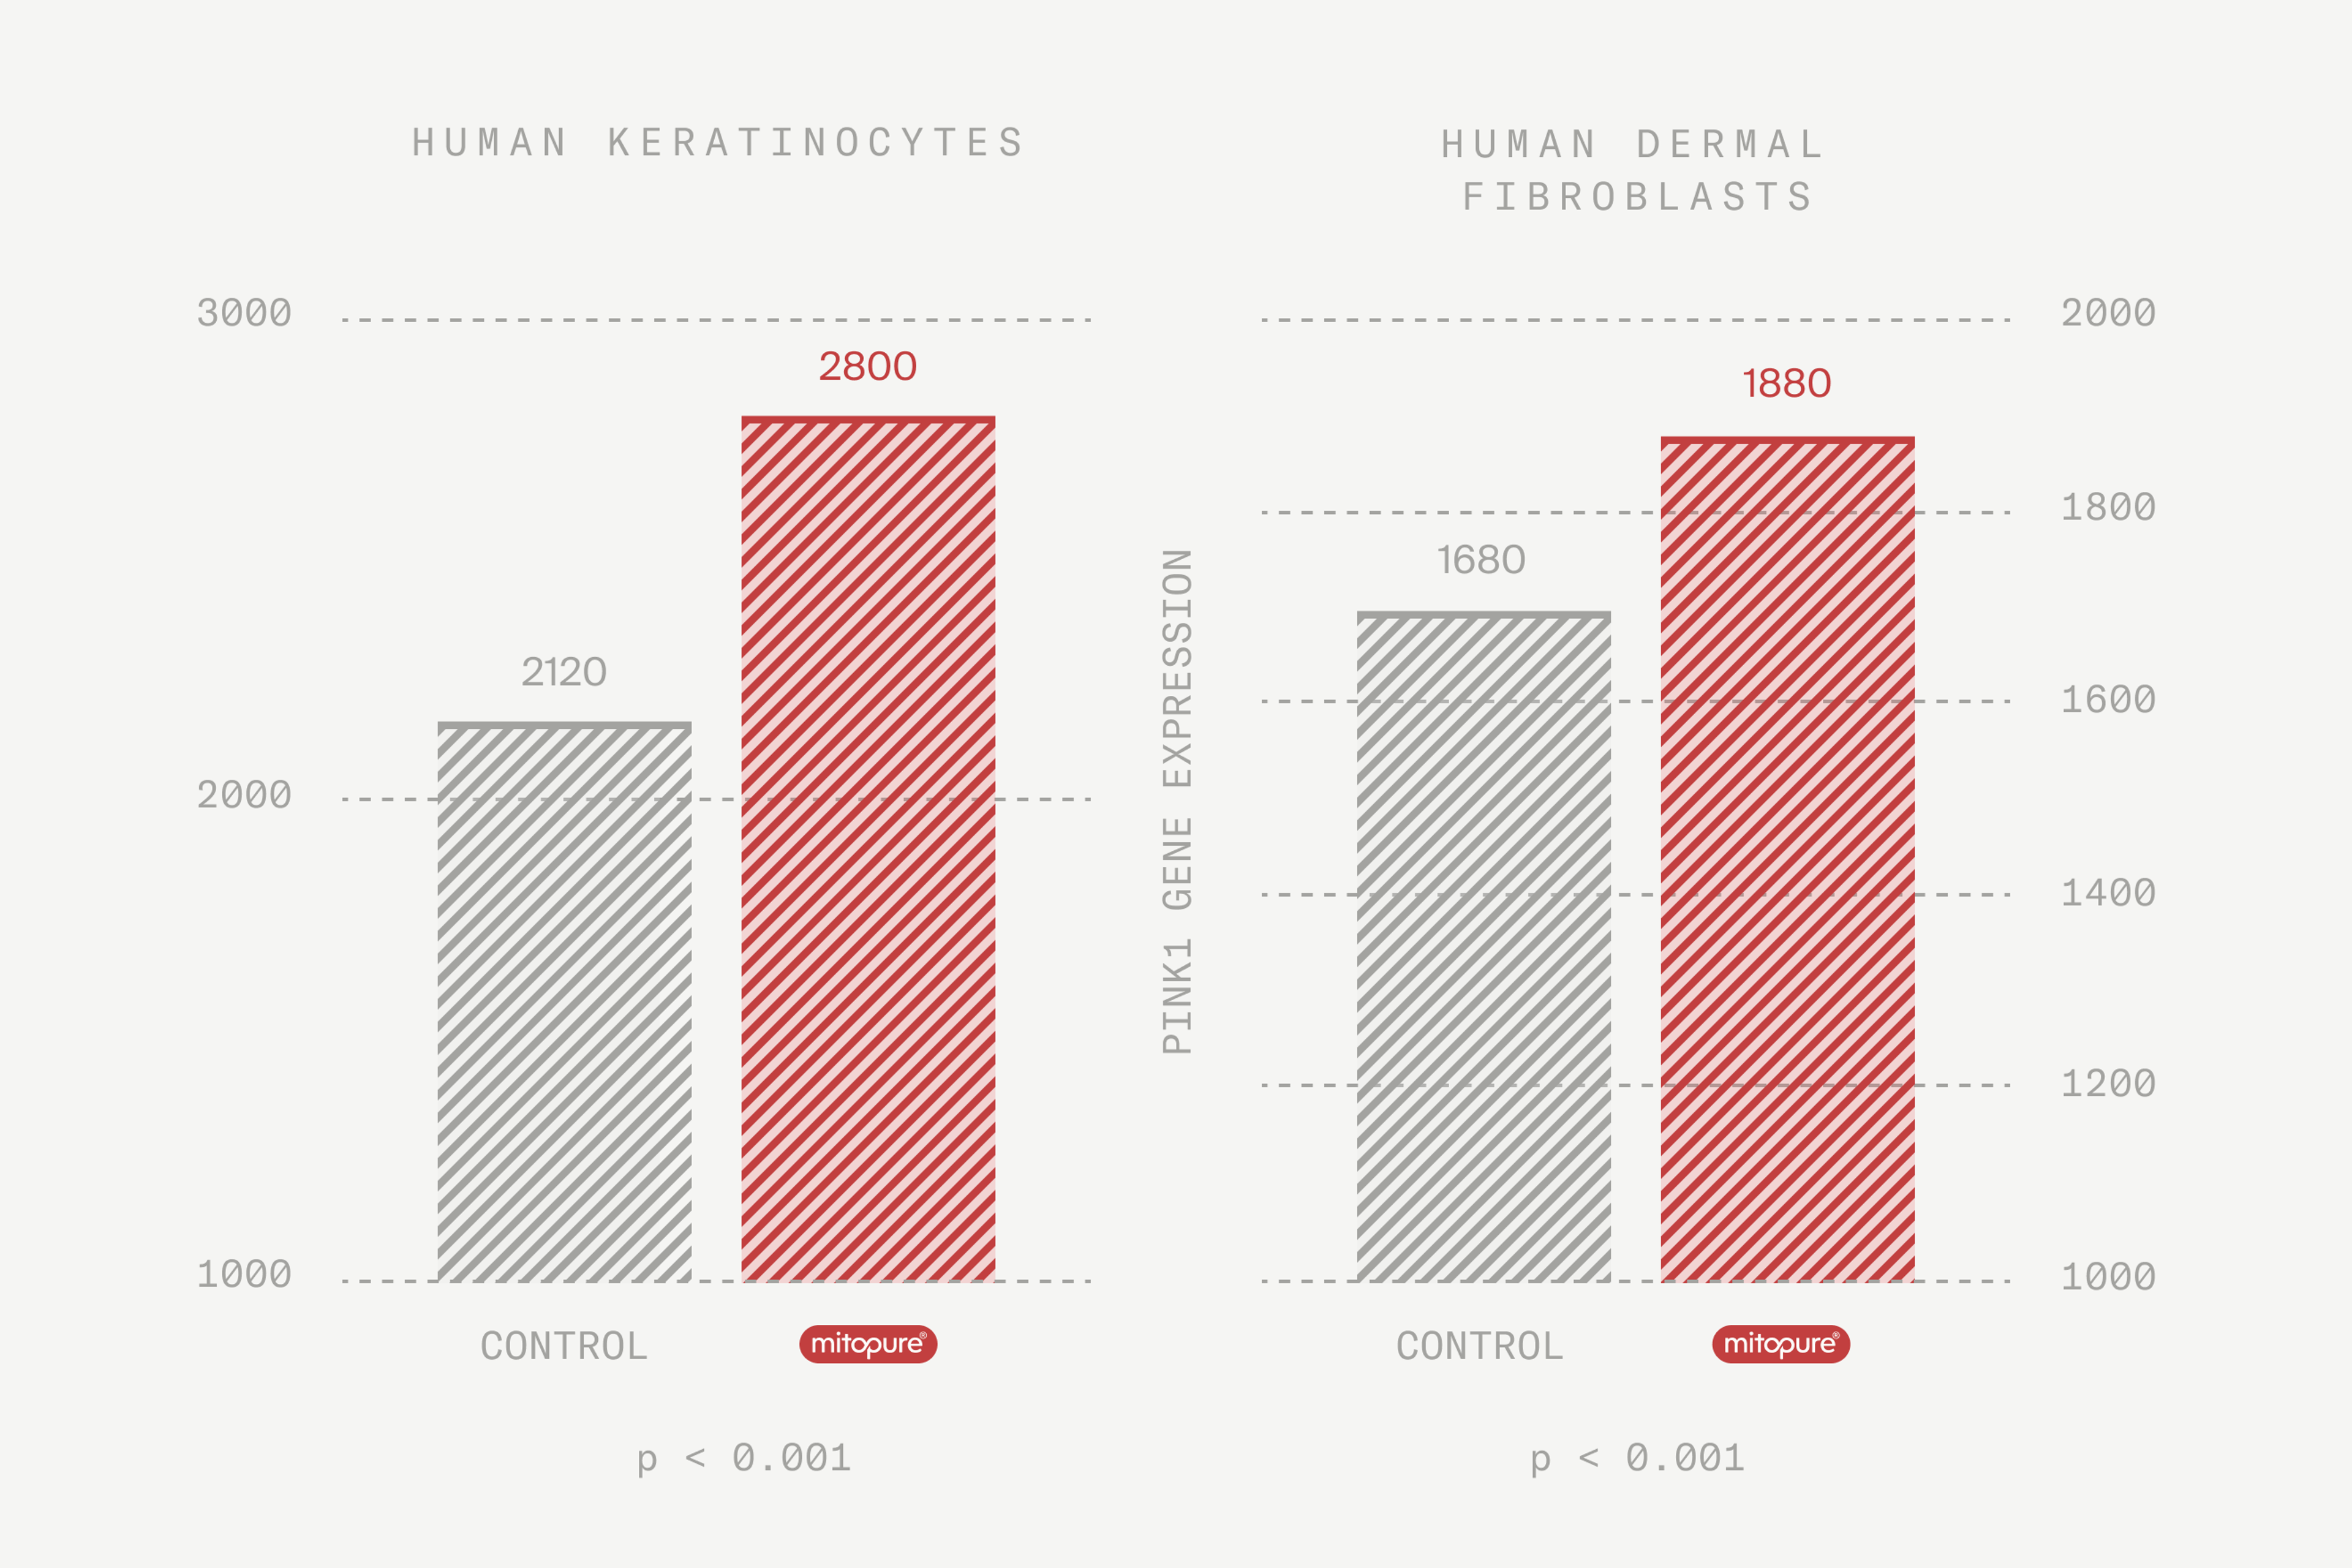

Mitopure® energizes skin cells

In our blog Skin health, aging and the cellular powerhouse we learned that skin needs a lot of energy to stay health and combat aging. Mitopure® has been clinically proven to support the pathway of energy production in cells that are at the heart of youthful looking skin.

What’s the evidence? Pre-clinical studies in human skin cells found evidence of increased activation of cellular renewal processes after 72 hrs. This increase helps maintain the recycling and replacing of old cellular powerhouses – which is good news for our skin!

Internal Amazentis study 1: Pre-clinical trial; Increased expression of mitophagy marker Park2 after 72 hrs. treatment; Blocked UV-mediated increase in inflammatory marker PGE2; UA at high dose of 1% induced mitochondrial abundance in reconstituted human epidermis (RHE)

Internal Amazentis study 2: Pre-clinical trial; Reduced collagen degradation and increased mitochondrial health biomarkers in human keratinocytes with Urolithin A; Increased markers of mitochondrial respiration